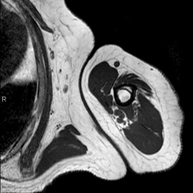

Exploració per a l'estudi de lesions a tendons, músculs i articulacions coxofemorals. Permet identificar de manera precoç l'artrosi de maluc. Resulta molt útil per detectar les bursitis i l'osteopatia dinàmica de pubis, freqüent en esportistes. La durada aproximada és de 20 minuts. No utilitza radiació ionitzant. - RM de Sacroilíaques